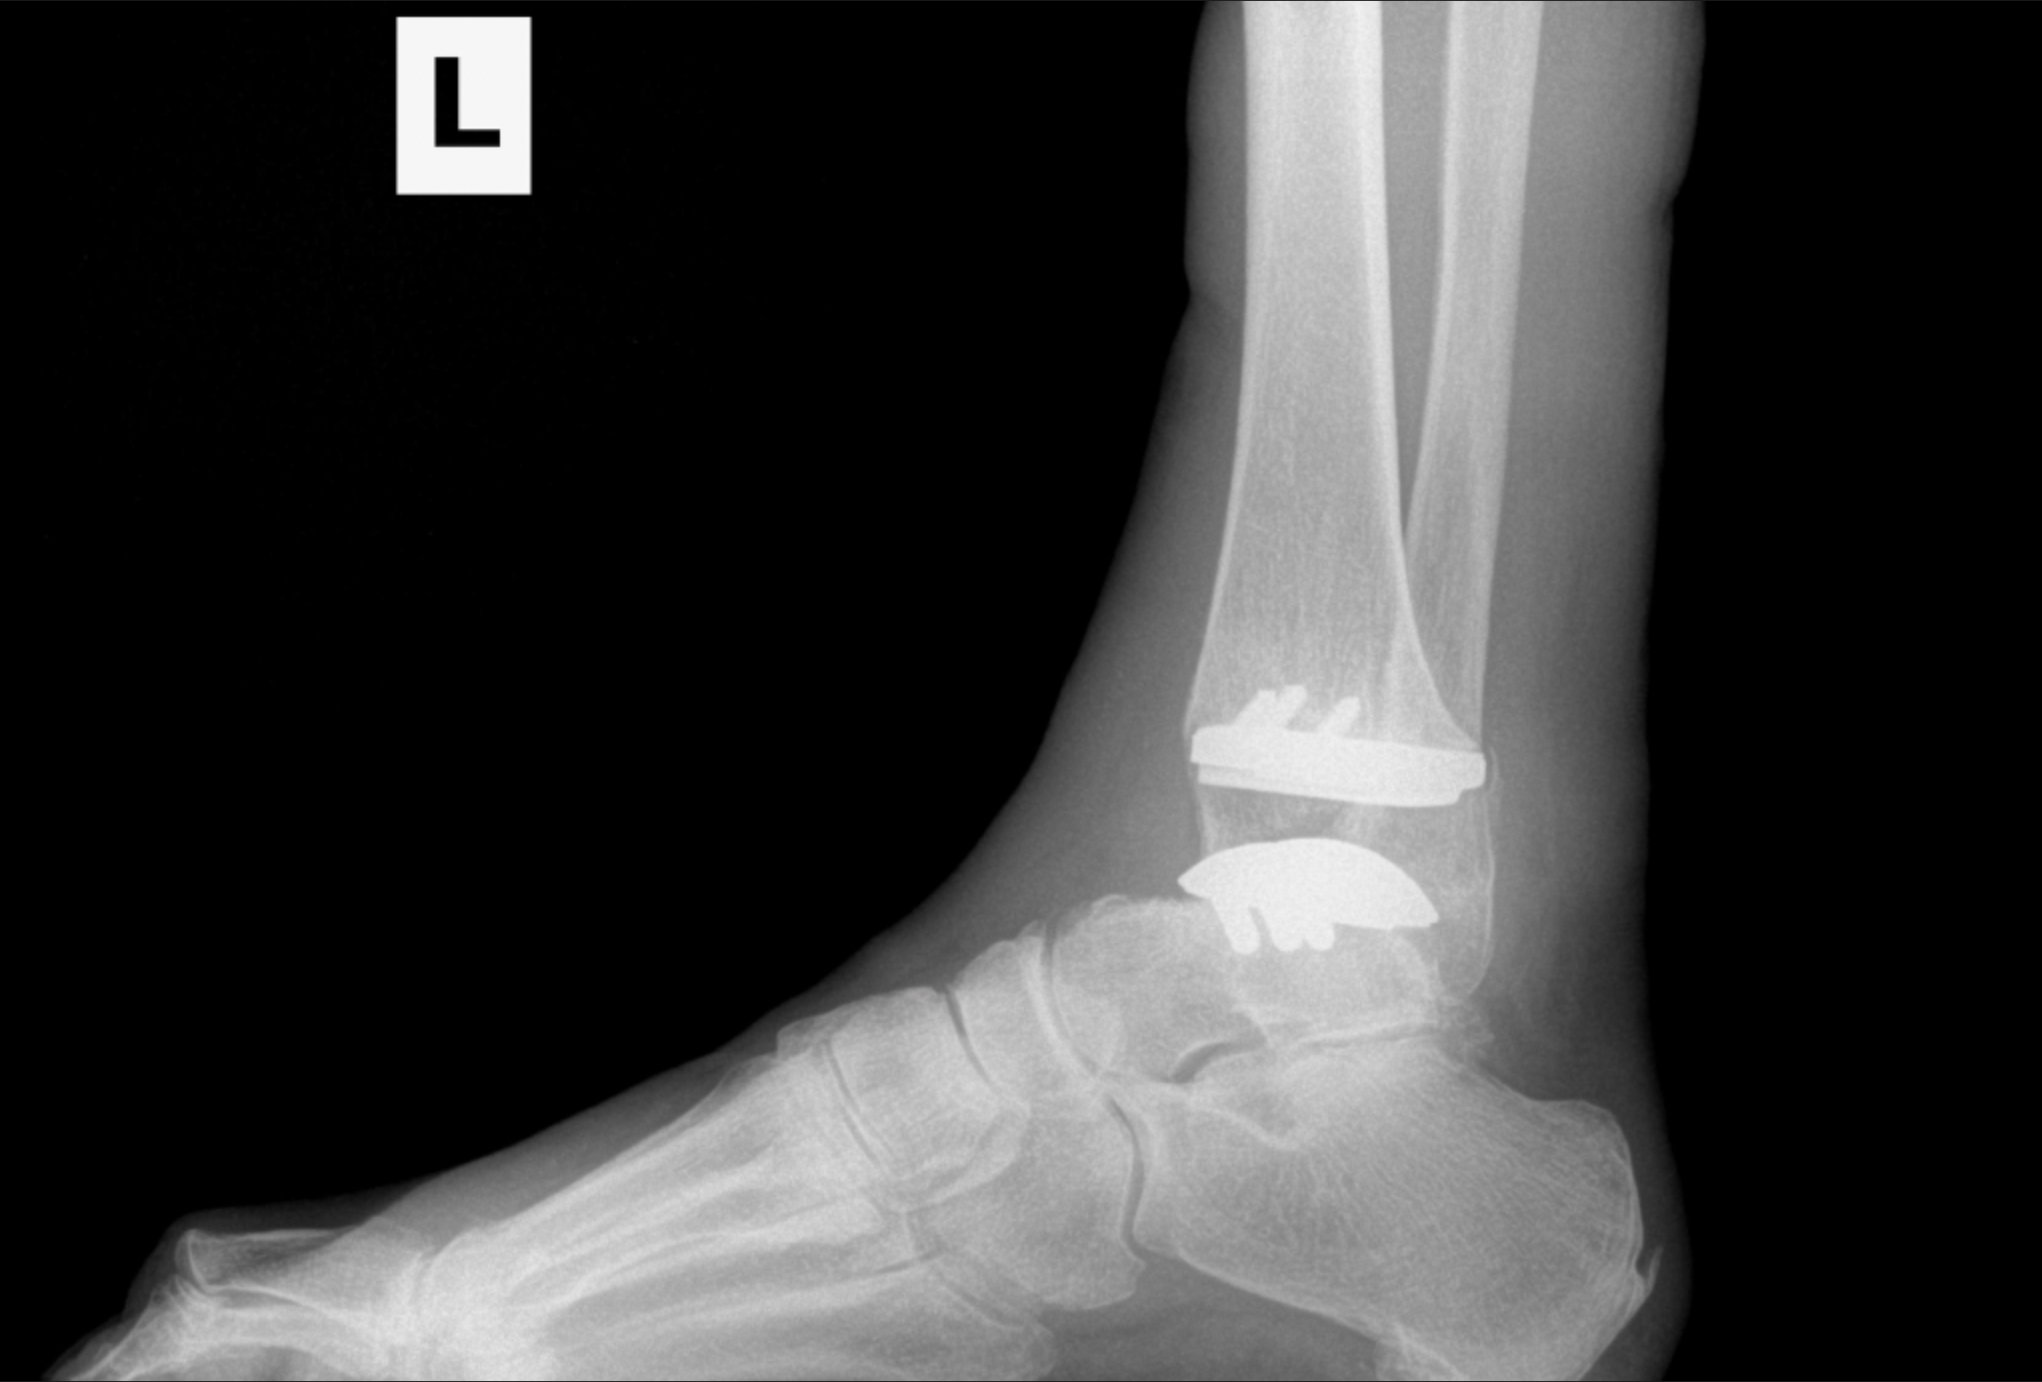

Foot & Ankle Replacement